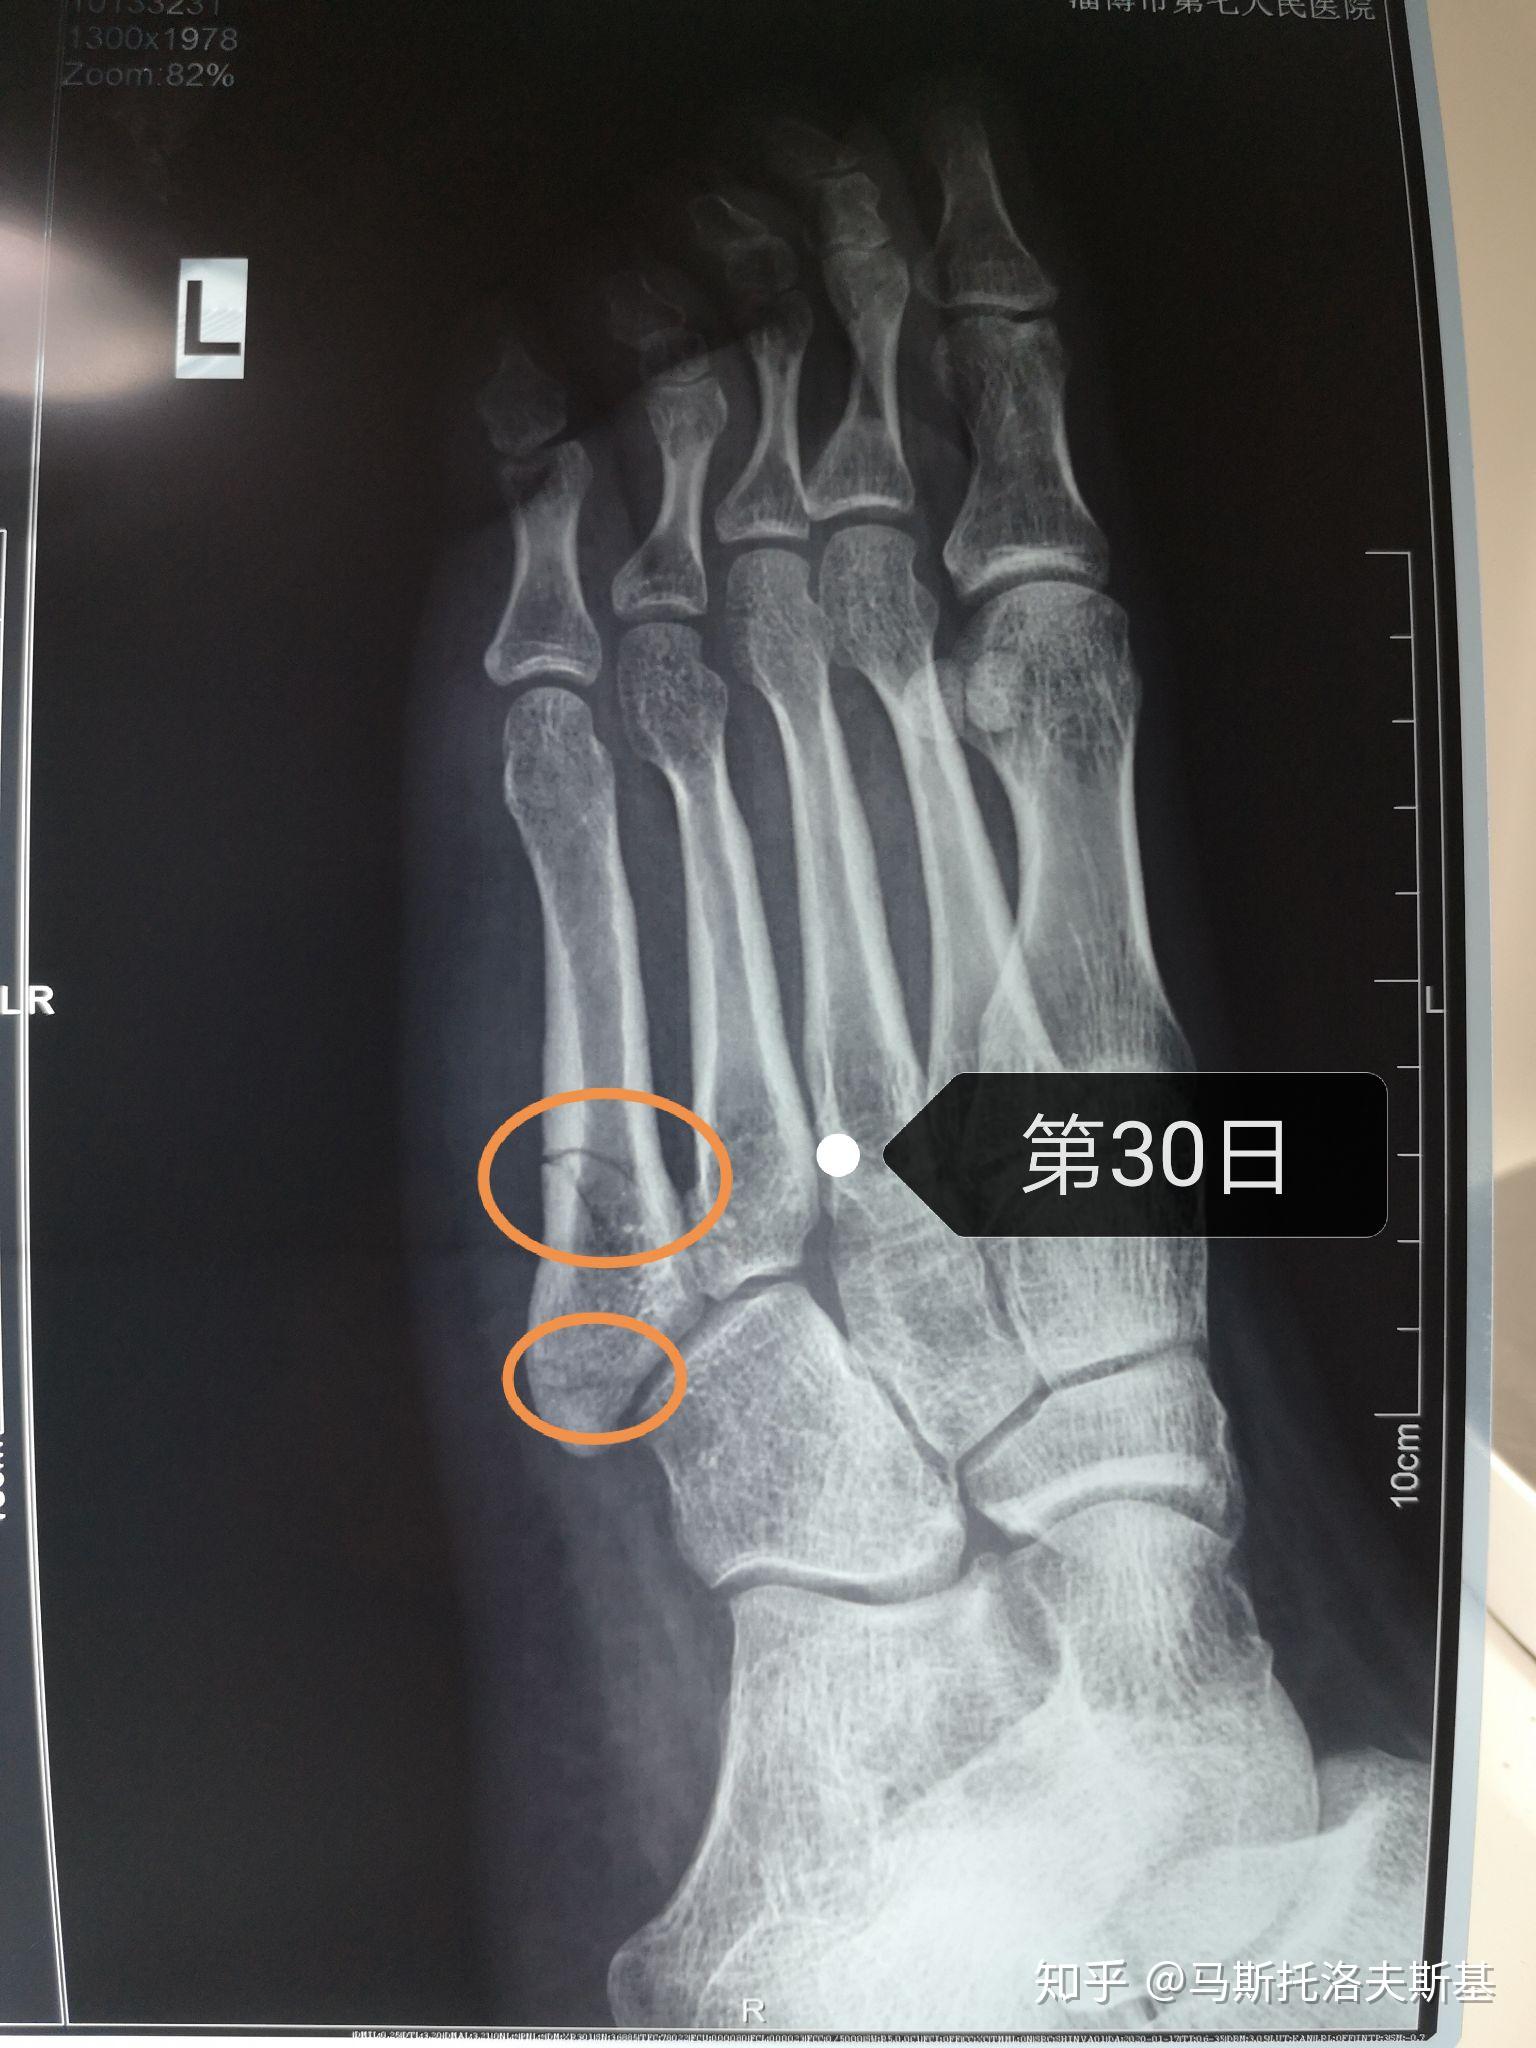

第五跖骨骨折1个月 从2月13到3.14,骨折30天了,满一个月了.